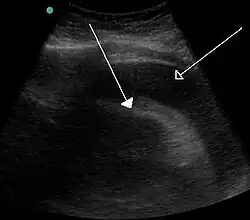

| A very large pericardial effusion resulting in tamponade as a result of bleeding from cancer as seen on ultrasound. Closed arrow – the heart; open arrow – the effusion | |